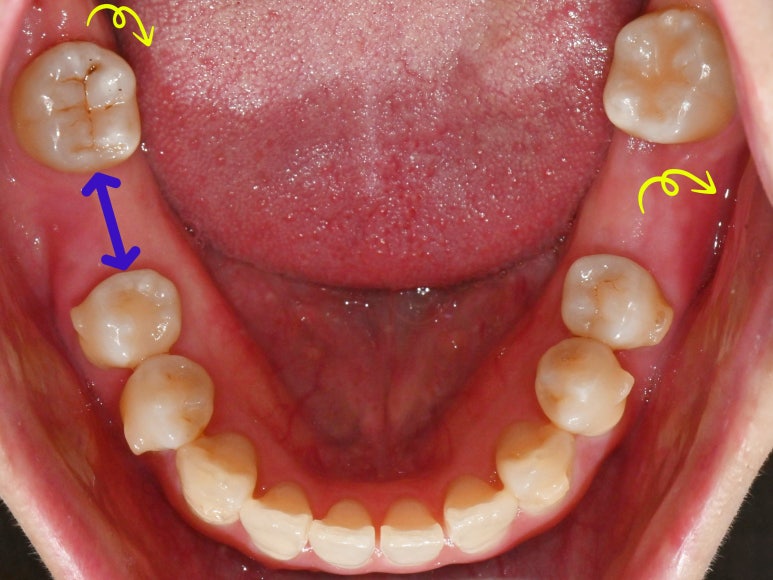

그리고 말씀드린 것처럼

부러진 채로 남아있던 이와 사랑니를 모두 뽑고,

임플란트 식립을 위한 공간을

확보하기 위하여 치아를 조금씩 이동시킵니다.

이 과정에서

삐뚤빼뚤한 앞니 총생도

자연스럽게 개선할 수 있습니다.

인비절라인을 이용하여

어금니에 임플란트를 심을 공간이

확보되었다면

그 자리에 픽스처를 심습니다.